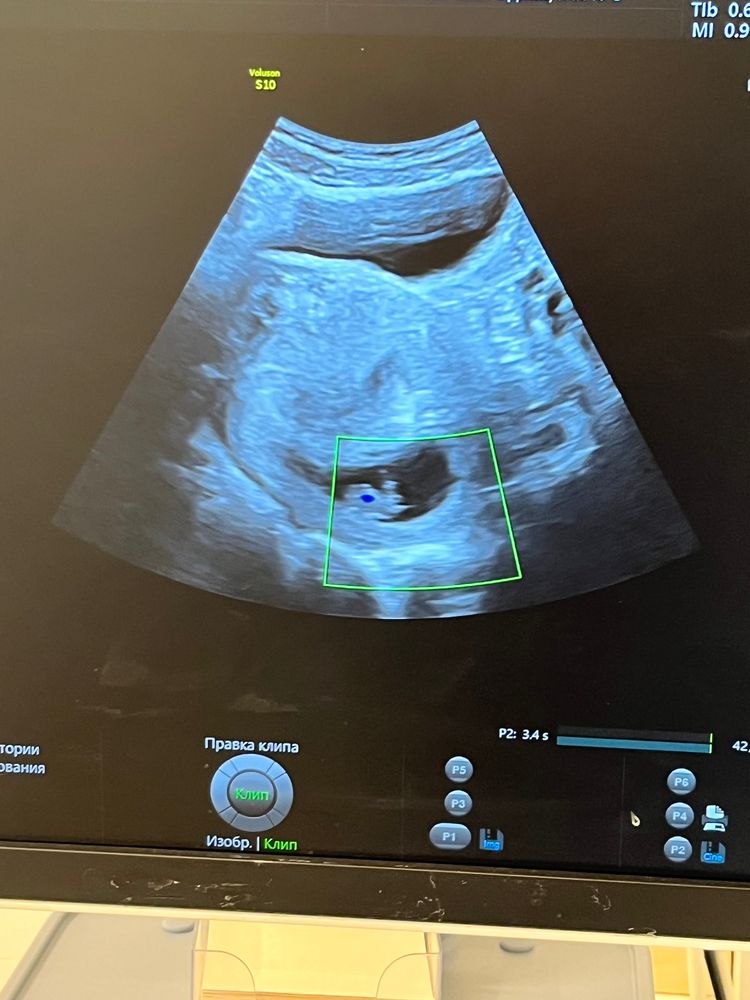

Беременность 9 недель

Беременность- 1 триместр ( только до 10 недель)